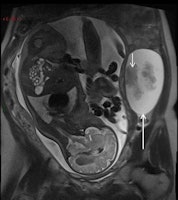

- Urolithiasis: Ultrasound is the first imaging test despite its substantial limitations. MR urography (MRU) differentiates physiological urinary tract dilatation from abnormal dilatation related to urolithiasis. In unresolved cases, CT remains a reliable technique for depicting obstructing urinary tract calculi in pregnant women.